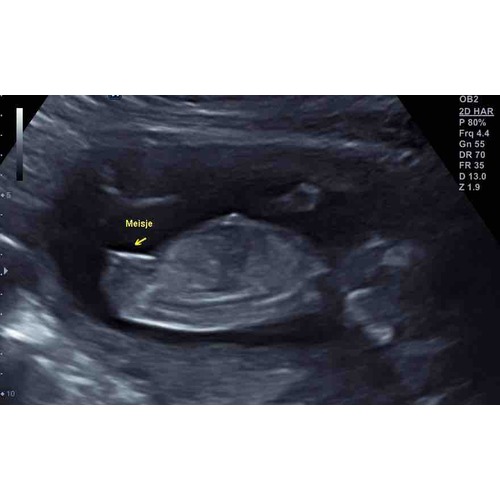

Maar op de eerste foto zijn de drie streepjes wel heel onduidelijk ik zal de mijne even erbij pakken..

Hier de 3 streepjes bij 15 weken en 3 dagen

Ik heb ook die streepjes. Maar de nub van jen2e foto zou ik al zeggen dat jongen is🙈 maar nu weet nog niemand zeker of jullie een zoon of dochter krijgen?